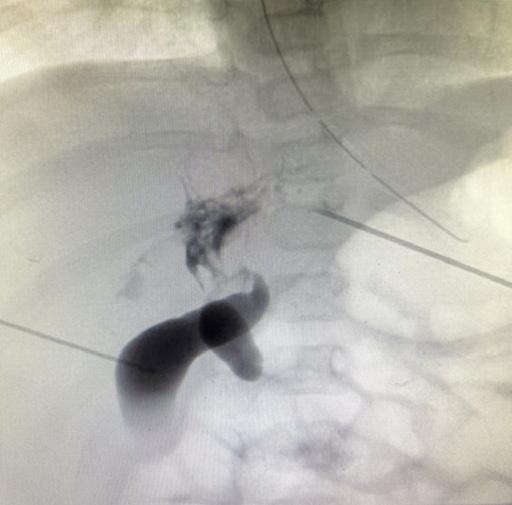

stenza di ittero e feci ipocoliche. Viene eseguita quindi una colangiografia transepatica che mostra una colecisti a contenuto acolico, comunicante con una struttura ovalare dell’ilo epatico identificata come coledoco, che tuttavia non comunica con le vie biliari intraepatiche né col tubo digestivo [Figura 4]. Le VBI sono irregolari, contengono dei microcalcoli e non sono cateterizzabili. Si pone diagnosi di atresia biliare atipica [Figura 5] [3].

4. Colangiografia transepatica che mostra una colecisti a contenuto acolico, comunicante con una struttura ovalare dell’ilo epatico identificata come coledoco, che tuttavia non comunica con le vie biliari intraepatiche e col tubo digestive.

5. Colangiografia transepatica che mostra VBI sono irregolari, contengono dei microcalcoli e non sono cateterizzabili.